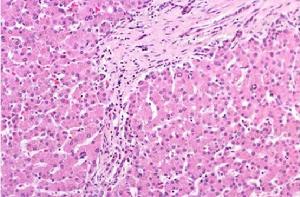

膽汁性肝硬化第一期,膽小管炎期,其特徵為肝小葉間膽管或中隔膽管的慢性非膿性炎症,膽小管管腔、管壁及其周圍有炎性細胞浸潤。主要為淋巴細胞、漿細胞。匯管區因炎性細胞浸潤而擴大,並有肉芽腫變,但肝細胞及界板正常。

第二期,膽小管增生期,膽小管由於慢性炎症的進行性破壞,代之以纖維組織,多數匯管區難以發現小葉間膽管,但有不典型小膽管增生,此期仍可見肉芽腫。肝小葉周圍毛細膽管極度擴張,含濃縮膽栓,毛細膽管破裂,形成膽糊,其周圍肝細胞腫脹,胞漿疏鬆呈透亮網狀,即羽毛樣變性。

第三期,瘢痕形成期,匯管區膠原含量增多而炎細胞及膽管減少,偶見淋巴濾泡伴生髮中心,中等大小匯管區纖維化最著,肉芽腫不常見,纖維分隔自匯管區向另一匯管區伸展,或向肝小葉延伸,由於碎屑樣壞死的並存以及淤膽,鐵、銅的沉積,引起肝細胞損傷,以致界板模糊不清。

第四期,肝硬化期,匯管區纖維隔互相擴展和連線,分割肝小葉形成假小葉,可見再生結節,一般為小結節性肝硬化,也可呈不完全分隔性,假小葉中央有壞死。

病理變化:早期肝體積常增大,表面平滑或呈細顆粒狀,硬度中等,相當於不全分隔型。肝外觀常被膽汁染成深綠或綠褐色。鏡下,肝細胞胞漿內膽色素沉積,肝細胞因而變性壞死,表現為肝細胞體積增大,胞漿疏鬆呈網狀、核消失,稱為網狀或羽毛狀壞死。毛細膽管淤膽、膽栓形成。壞死區膽管破裂,膽汁外溢,形成“膽汁湖”。門管區膽管擴張及小膽管增生,纖維組織增生及小葉的改建遠較門脈性及壞死後性肝硬化為輕。伴有膽管感染時則見門管區及增生的結締組織內有多量嗜中性粒細胞浸潤甚至微膿腫形成。